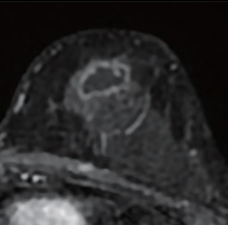

55-year-old patient with triple-negative breast cancer (TNBC) from training set

Liang et al.’s AJR manuscript included patients with TNBC undergoing NACI and who underwent breast MRI including dynamic contrast enhancement before treatment and after the first treatment cycle (i.e., early NACI), including a single-center training set of 90 women (mean age, 49 years; January 2018 to September 2024) and an external test set of 29 women (mean age, 46 years; date range unavailable) from publicly available trial data. Two radiologists evaluated MRI features, including percentage enhancement (PE) reduction, representing semiquantitative assessment of relative expansion of intralesional nonenhancing components after early NACI. A model for predicting pCR on definitive surgery after NACI completion was constructed in the training set using independent predictors from multivariable logistic regression analysis and was evaluated in the external test set.

Ultimately, Liang and colleagues’ model constructed to predict pCR in patients undergoing NACI for TNBC combined tumor unifocality on pretreatment MRI and early tumor shrinkage ≥ 37% and percentage enhancement reduction on MRI performed after one cycle. In an external test set, the model achieved AUC of 0.88, sensitivity of 74%, and specificity of 90%.